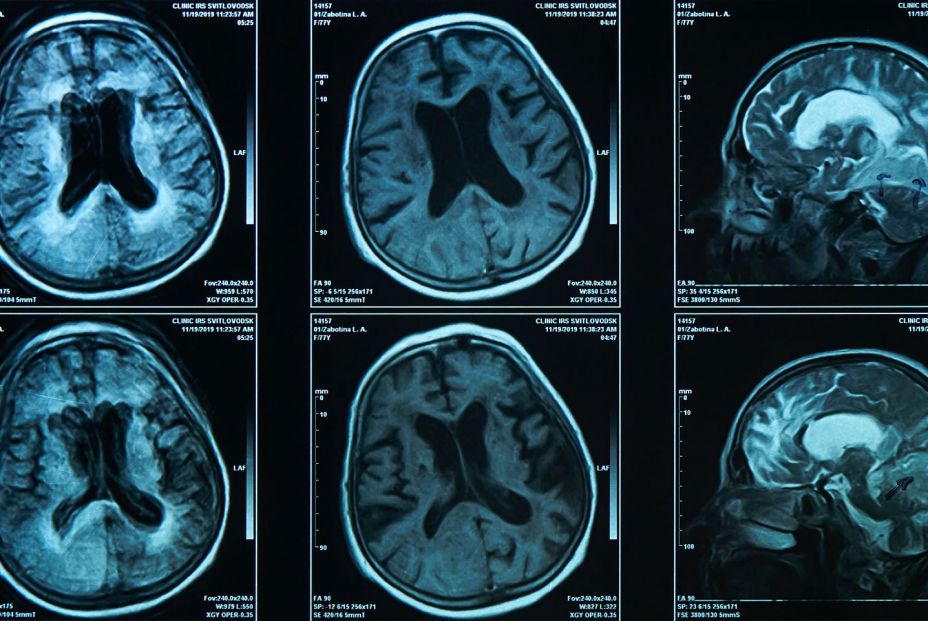

Investigadores de la Clínica Mayo (Estados Unidos) han desarrollado una nueva herramienta que permite estimar el riesgo de una persona de desarrollar problemas de memoria y pensamiento asociados con la enfermedad de Alzheimer años antes de que aparezcan los síntomas.

El nuevo modelo predictivo combinó varios factores, como la edad, el sexo, el riesgo genético asociado al genotipo APOE y los niveles de amiloide cerebral detectados mediante tomografía por emisión de positrones (TEP). Con estos datos, los investigadores pueden calcular la probabilidad de que una persona desarrolle deterioro cognitivo leve (DCL) O demencia en un plazo de 10 años o a lo largo de su vida. De todos los predictores evaluados, los niveles de amiloide cerebral detectados mediante TEP fueron el factor con mayor influencia en el riesgo de desarrollar DCL y demencia a lo largo de la vida.